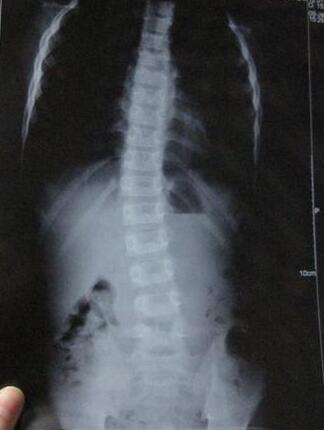

强直性脊柱炎是一种常见多发病会引起脊柱部疼痛、下肢麻木、发凉 ...

我们需要尽早了解强直性脊柱炎,随着这种疾病的出现几率升高大家 ...

目前青少年强直性脊柱炎的早期症状有啥?强直性脊柱炎常见于16~3 ...